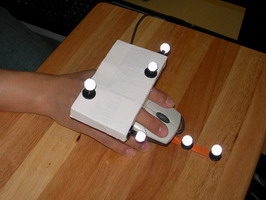

b) Experimental setup

b) Experimental setup

The experimental task was to define a straight vessel-free path from the cortical surface to the targeted tumor using (a pen-like) probe. Because of the complex anatomical structure of the human brain and the topology of key blood vessels, defining such a path for insertion of probes and tools can be a challenging task in practice. For this task, we visualized the segmented brain vasculature with a simulated tumor at positions of varying difficulty of reaching, as shown in Figure a. Subjects were provided with hand-coupled motion cues as they manipulated the volume and probe (Figure b)). Two tangible objects were used as input devices: a small plastic skull to manipulate the orientation and proximity (zoom) of the vasculature, and a replica of a biopsy probe used to locate the tumor. Once the subject was satisfied with the probe position, a foot step, sensed by an electronic game controller dance pad, is used to end the trial. This avoided the risk of introducing jitter to the probe position, which may have resulted otherwise had a manual button press been required.

Depth Slider is a physical

slider manipulated by the non dominant hand and used

in cooperation with a regular mouse in the dominant hand.

The slider adds the control of depth to the mouse.We re-implemented the original Rockin’ Mouse design of Balakrishnan

et al., modifying a regular mouse by adding a

curved foam base with a flat bottom for tilting, and attached

a number of retro-reflective markers for tracking the position